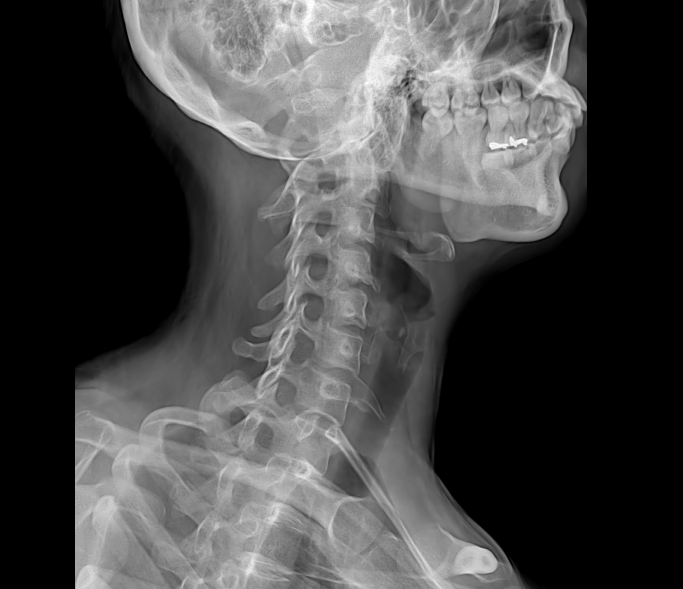

• Clinical Images